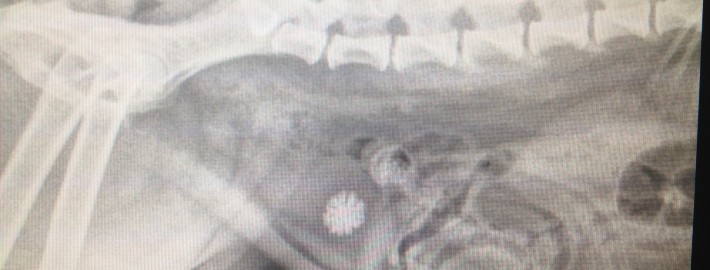

Voici la radiographie de Hercule Boily, un chihuahua croisé de 5 1/2 ans. Un gros calcul urinaire est visible au centre de la vessie.

À voir la forme irrégulière du calcul, on constate aisément que celui-ci est très irritant pour la vessie.